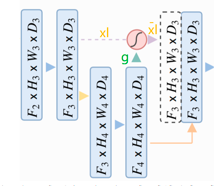

其中g为门控信号,xl为encoder对应的feature map,g来自于decoder的下一层,所以g尺寸大小是这一层的1/2。x完成Attention之后和g一起concat再进入下一层decoder。

在上面这个图中,黄色的xl如果在unet中是要直接通过跳跃连接和绿色的g上采样的结果进行concat,但是在attention unet中先对xl和g转成一样的size,然后相加经过relu、sigmoid得到attention coefficients。